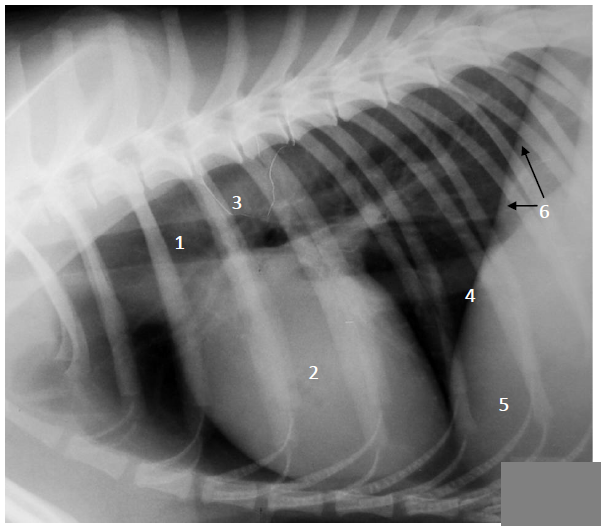

Analise na imagem radiográfica abaixo (radiografia laterolateral do tórax de um canino) as estruturas/regiões anatômicas numeradas de 1 a 6.

Assinale a alternativa que apresenta corretamente a denominação dessas estruturas/regiões.